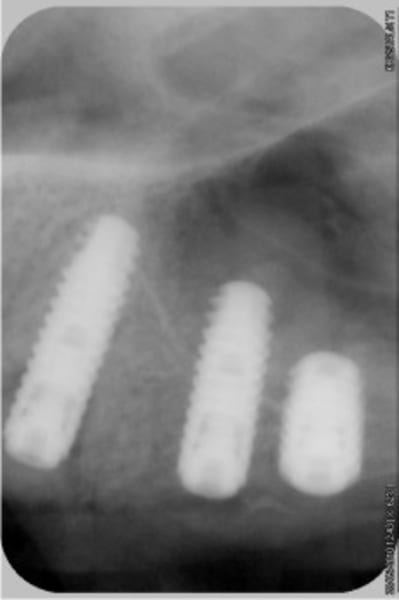

La pano, excusez, j'ai perdu l'habitude d'eugénol...

NB: les implants distaux gauches vont être retirés, il étaient déjà là avant que je n'intervienne.

Bonjour mes CHERS AMIS, ouverture à 5 mois, et comme vous êtes sympas, je fais un lambeau (la patiente me pardonnera)

deux trois photos pour montrer que crédulité et optimise ne vont pas de pair....

ah ! oui, le VITAL OS à super bien fonctionné ici.

c'est bien mené, on voit nettement la différence entre l'avant et l'après, surtout le volume des crêtes.